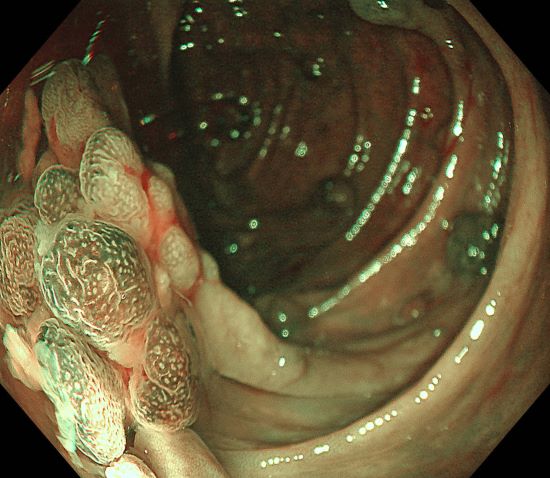

Polymorphic multicolored polypoid elevations in ascending colon

2. WLI observation

#Structure enhancement: A3